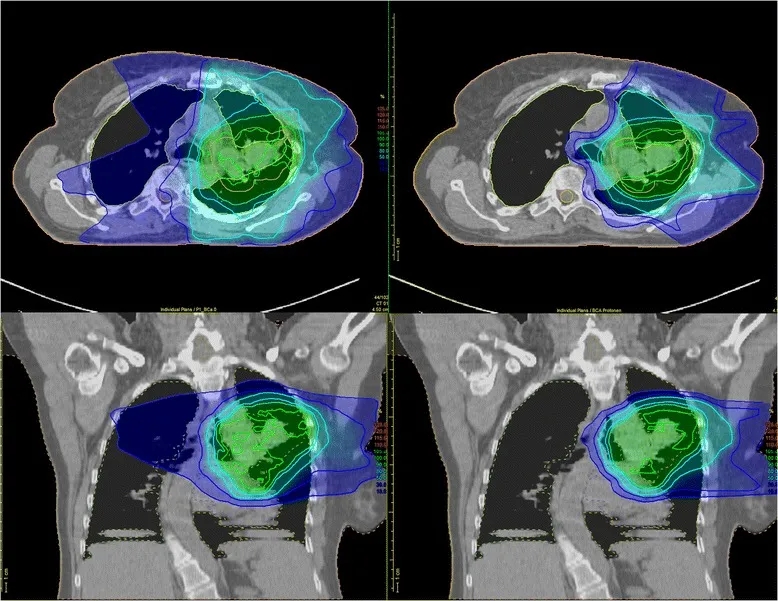

例如,针对局部晚期非小细胞肺癌(NSCLC)患者的剂量分布显示:与调强光子放疗(IMRT)相比,质子治疗对危及器官(OAR)的剂量显著更低,传统放射疗法会将辐射波及肿瘤周围健康组织(详见下图左),而质子疗法则能将大部分辐射集中于肿瘤靶区(详见下图右)。

▲图源“Trials”,版权归原作者所有,如无意中侵犯了知识产权,请联系我们删除